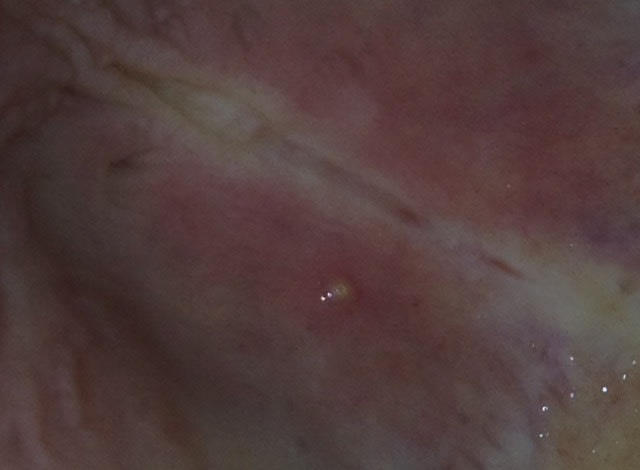

voici des jolies photos, la patiente est une jeune femme de 35 ans, non fumeuse avec une bonne hygiène,

elle présente une lésion sur le palais dur

2 semaines après il ne reste plus qu'un point blanc de la taille d'une épine

Bonjour, la bulle est partie, puis revenue dans les mêmes proportions. N'est-ce pas un peu fort de pratiquer être biopsie pour 2 mm qui vont et viennes ? Cela me semble très bénin

Bonjour, après extraction de la liaison bulleuse et anaph., voici les résultats :

- épulis angiomateux

Donc aucun critère de malignité.